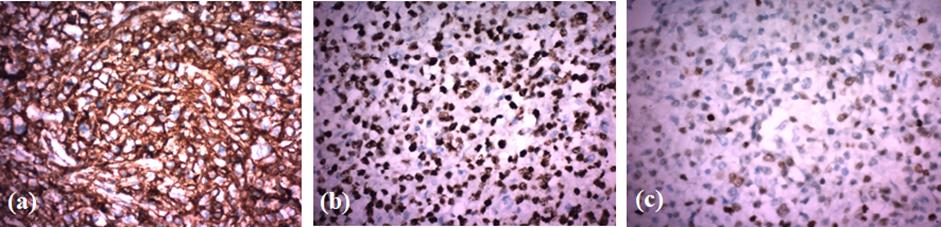

Figs. 1a and b. CECT abdomen axial and coronal images respectively showing aneurysmal dilatation of distal ileum marked with arrow.

Figure 1